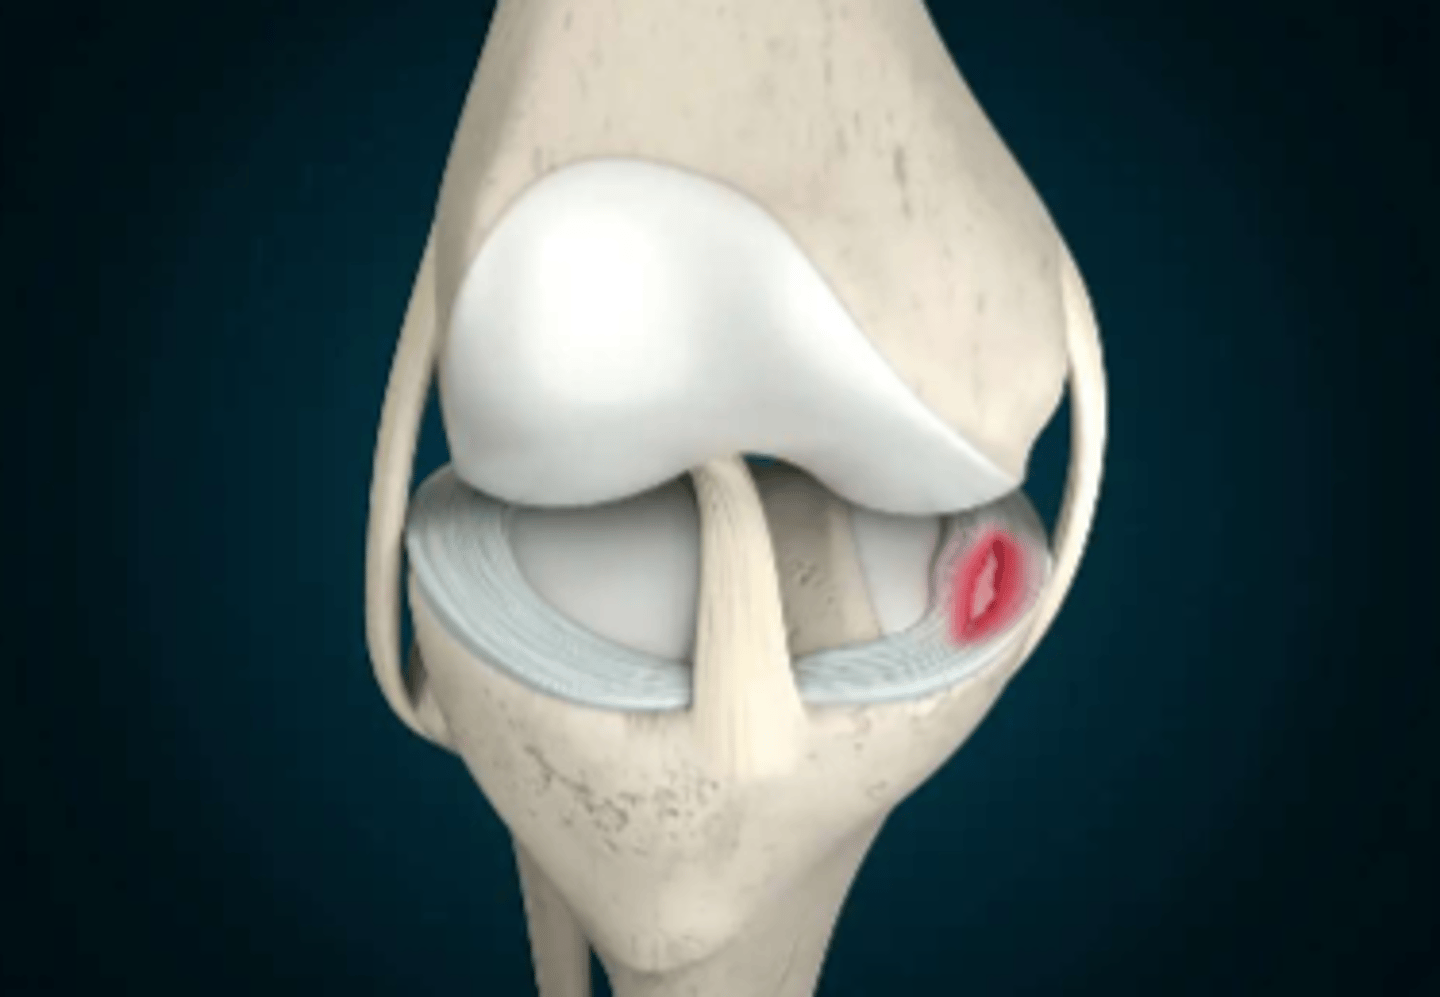

How does a meniscus (pads of knee joint) tear heal

fibrocartilage, slow healing